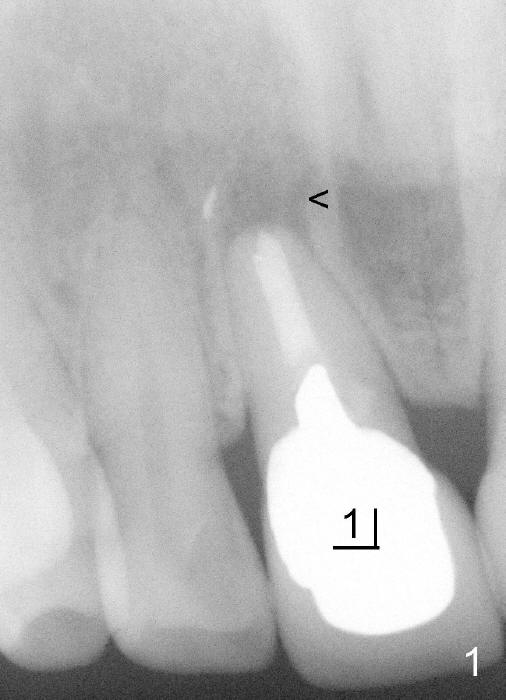

其实临床情况千变万化,处理方法可以有所变化。朱女士六十来岁,后牙缺失严重,右上中切牙根管治疗重做后感染复发(图一*:根尖阴影),但是没有任何症状,不久牙冠脱落,根尖瘘道(图二箭头)。估计炎症不是那么严重,拔牙后,常规牙槽窝处理,开始即刻植牙。处理颊侧根尖缺失办法,不是植骨,理由是植骨和植牙同时进行,增加身体负担,它们都是异物。

植牙窝适当远离颊侧根尖缺失处,植牙过程可能自行缩小,关闭缺失,最后身体自然修复。

好了,让我们看结果。图三显示即刻植牙,六个月后根尖瘘道消失(图四),愈合基台(healing abutment)近远中牙龈乳头(*)与术前没有多大区别,说明即刻植牙在愈合中维持牙龈外形。今后牙龈谅比正常,我们下次见。